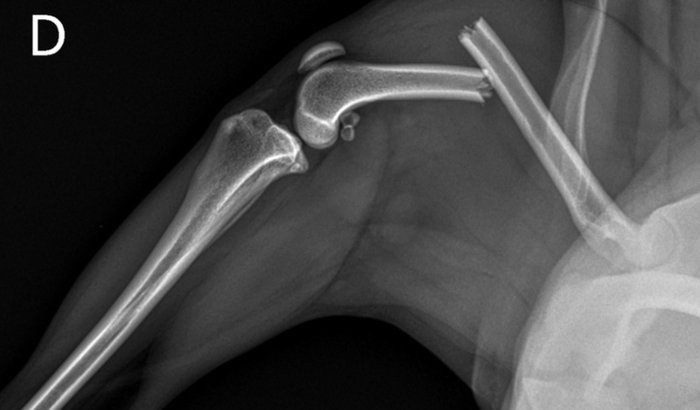

O Leão, nosso cachorrinho de apenas 2 anos, sofreu um acidente recentemente: ele pulou da janela do carro quando voltávamos de um final de semana no sítio e, infelizmente, fraturou o fêmur da pata traseira direita. 😔